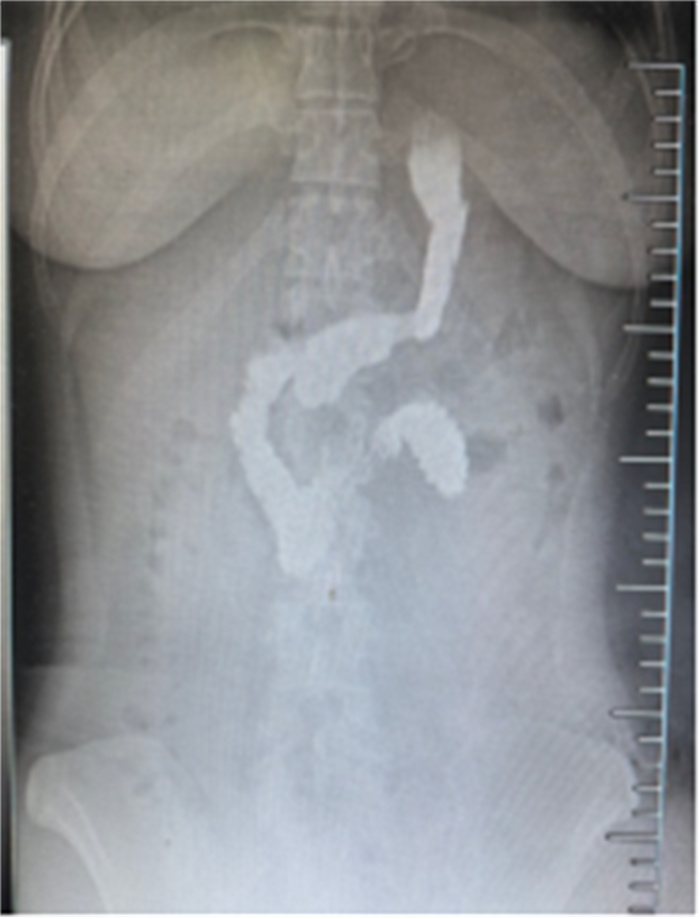

日前,首都医科大学附属北京天坛医院普外科、麻醉科、手术室多部门协同配合,为一位体重达210斤、BMI(身体质量指数)达38.5㎏/㎡的重度肥胖女性患者完成单孔腹腔镜下袖状胃切除术。据悉,这也是北京天坛医院完成的首例此类手术。

“我们根据患者的情况,为她选择了单孔腹腔镜下袖状胃切除手术。”普外科主任医师闫文貌介绍,这种手术需要经肚脐切开一个2-3厘米的小口,通过专用单孔器械,在体外完成腹腔内手术操作,由于切口小,术后几乎看不到瘢痕,而且疼痛轻、恢复快,同时对于医生而言,术中非常容易取出手术标本。但同时由于手术中腹腔镜和操作器械都是经肚脐单一切口进入腹腔,容易造成器械之间的相互干扰,形成“筷子效应”,尤其是肥胖患者腹壁明显增厚,更增加操作难度,需要术者有丰富的腹腔镜手术经验和足够的耐心。

9月27日,在麻醉医生周志刚、岳红丽和手术室蔡晓珊等全力配合下,普外科闫文貌、汪鑫、李仕一为这位患者进行手术。手术过程非常顺利,患者术后第二天开始下床活动,空腹血糖恢复正常,第三天即可以饮水,术后第六天顺利出院。